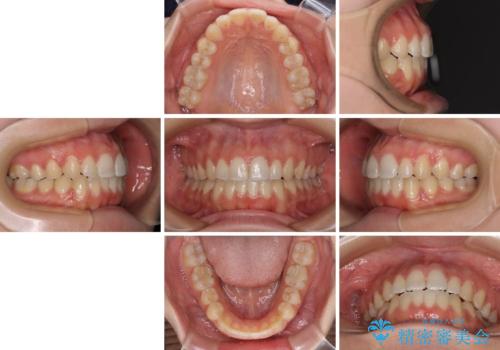

- 前歯の上下スペースによる食べにくさを気にして来院された患者様です。

インビザラインにより上下の前歯の隙間を閉じていくこととしました。

前歯のデコボコの解消と並行して上下の奥歯を圧下させるようにすることで、前歯を接触させるように計画しました。

上下の隙間に舌が入り込むことがオープンバイトの原因であったため、舌の筋肉のトレーニングも並行して行い、後戻りの抑制を図りました。